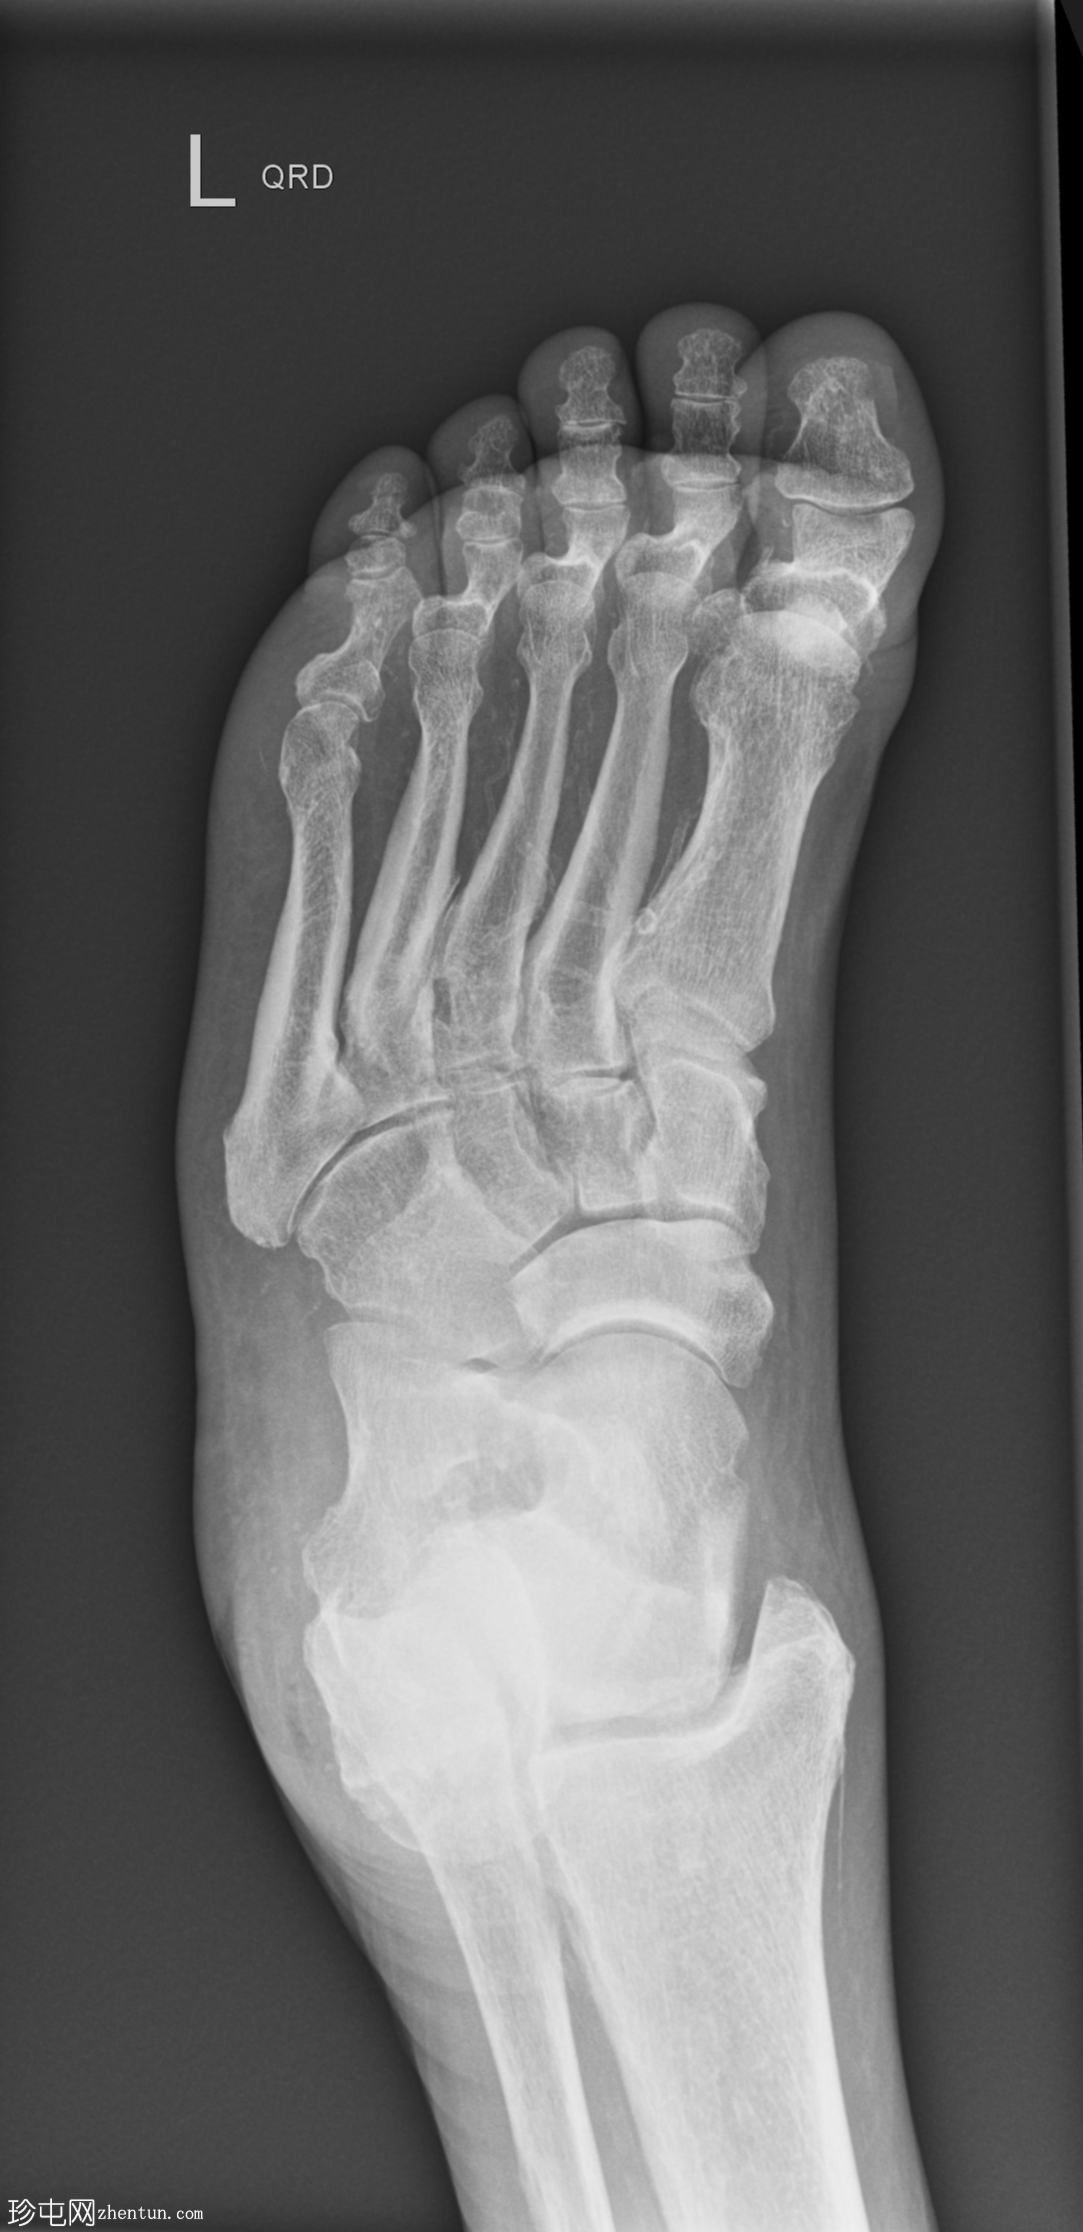

X光片

正位片

跖趾关节爪状趾畸形

动脉钙化

爪状趾畸形是指小趾跖趾关节过度伸展,导致近端指间关节(PIP)和远端指间关节(DIP)屈曲。